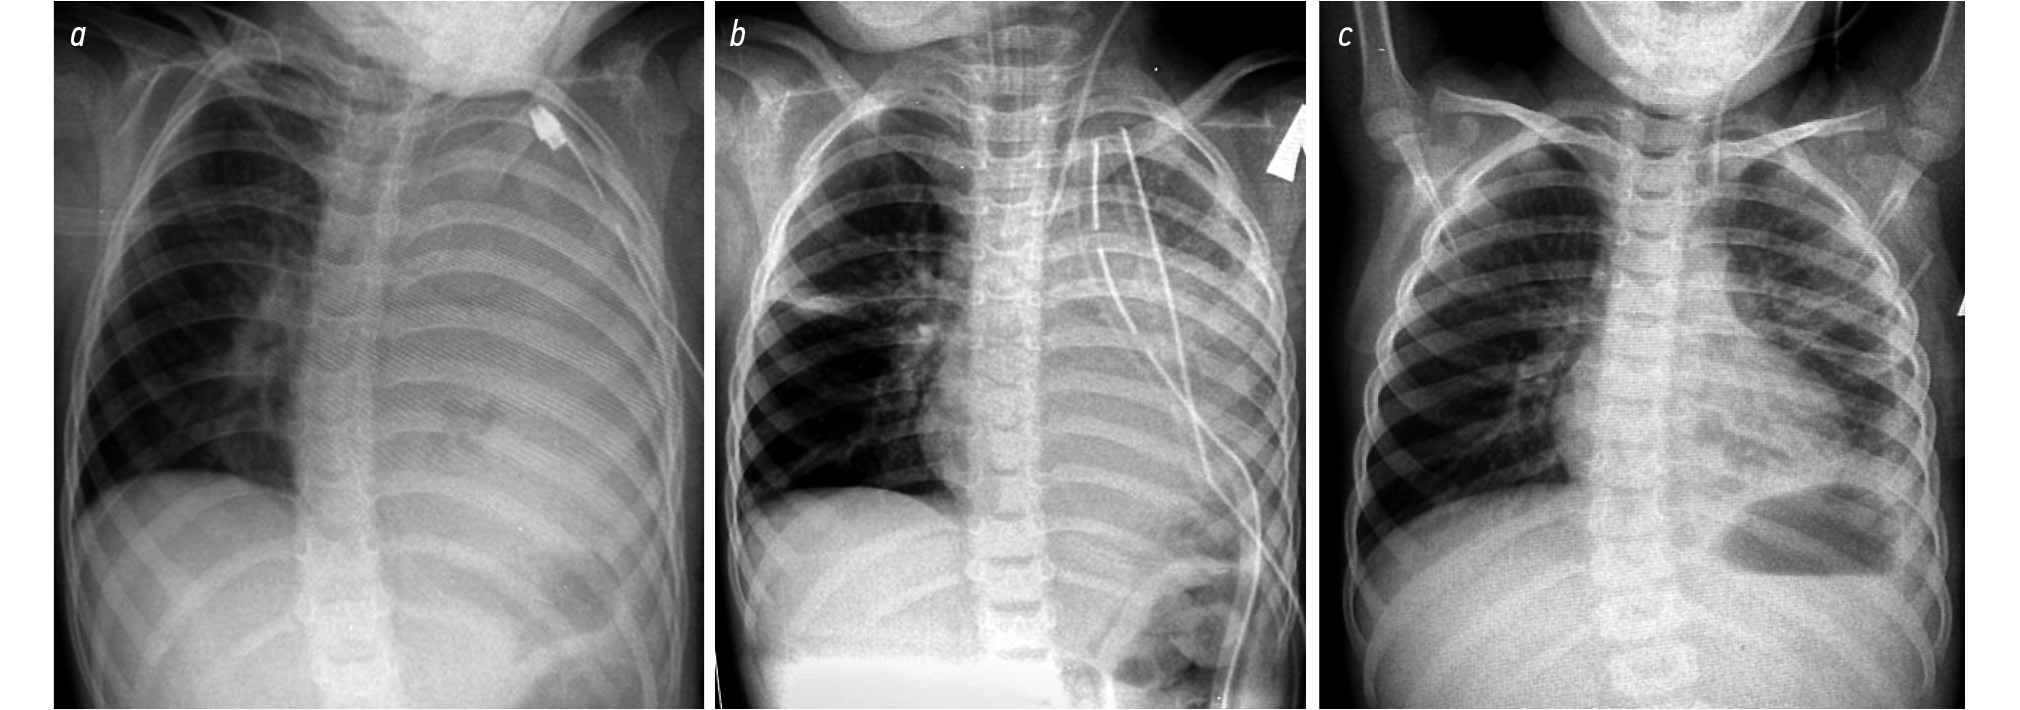

Наиболее демонстративным признаком эффективности применения ПФ послужила динамика рентгенологической картины. Если по критерию реэкспансии лёгкого в 1-е сут после операции значимого различия между пациентами двух групп не выявлено, то рентгенологические признаки регресса фибриноторакса в основной группе констатировались раньше: на (2±0,4) день лечения (рис. 9, 10) и на 3–12 мес. после лечения.

Рис. 10. Рентгенограммы органов грудной клетки больной Г., 3 лет (контрольная группа): a — до операции, b — на 1-е сут после операции; c — на 7-е сут после операции.

Fig. 10. Radiographs of the chest organs of patient G., 3 years old (control group): a — before surgery, b — on day 1 after surgery; c — on day 7 after surgery.